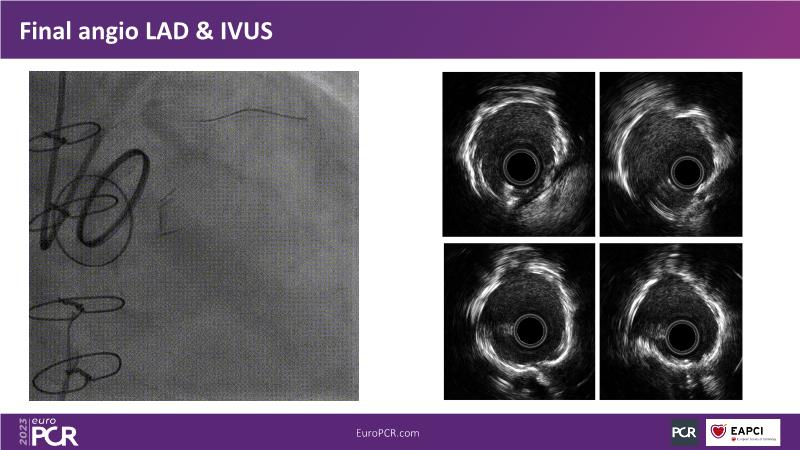

• To understand why you can count on customised drug delivery platform of DES+DCB in complex settings with imaging-based evidence through case presentations